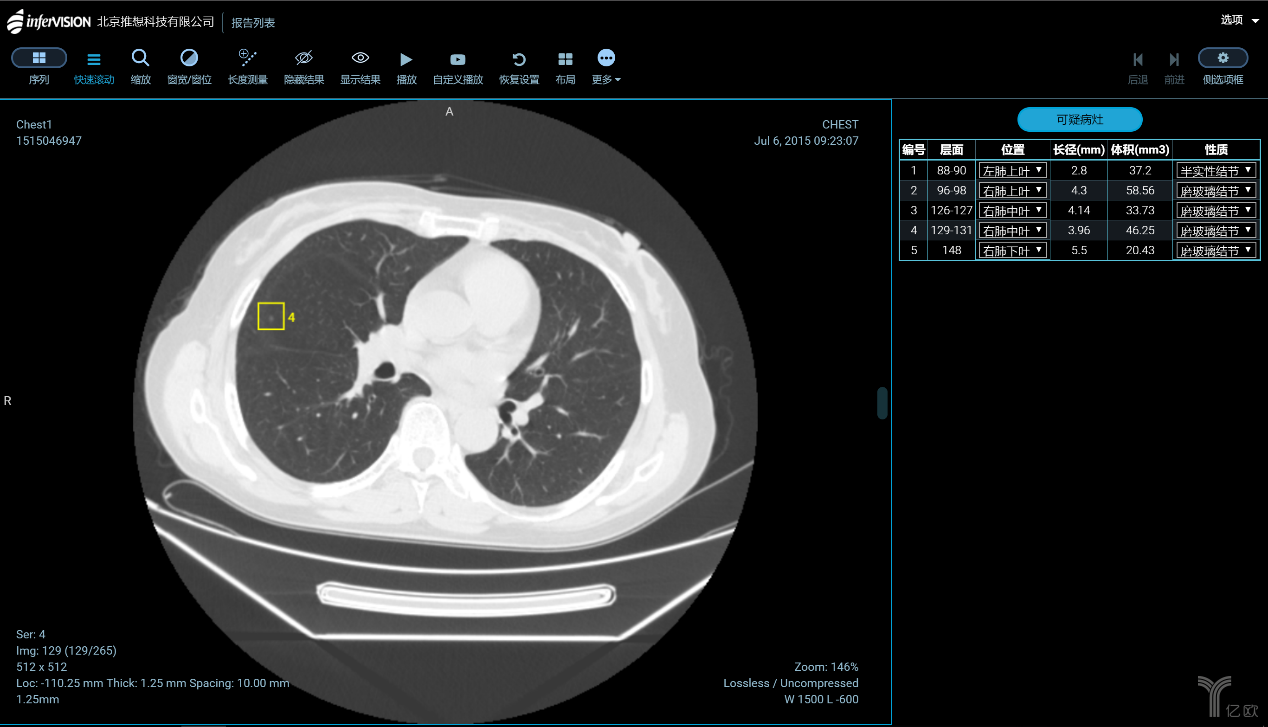

肺結(jié)節(jié)的識(shí)別與診斷,是大部分企業(yè)算法模型訓(xùn)練的起點(diǎn)。一方面是因?yàn)橹袊?guó)是肺癌大國(guó),肺部影像數(shù)據(jù)量最充足;另一方面是由于全球針對(duì)肺結(jié)節(jié)識(shí)別的研究最為成熟。國(guó)內(nèi)在肺癌診斷與篩查方向進(jìn)展較快的,主要有推想科技、圖瑪深維、健培科技、體素科技、依圖醫(yī)療、匯醫(yī)慧影、深睿醫(yī)療、視見(jiàn)醫(yī)療、華潤(rùn)萬(wàn)里云、零氪科技等。除了肺癌之外,針對(duì)乳腺癌、肝癌、鼻咽癌、腦卒中的自動(dòng)檢測(cè)也正在成為焦點(diǎn)。

智能CT輔助篩查產(chǎn)品(AI-CT)功能界面(圖片來(lái)源:推想科技)